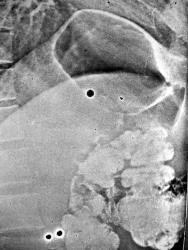

На операции под правым куполом диафрагмы, между ним и печенью, обнаружена тонкостенная полость с воздухом, ни с каким органом не связанная. В том и непонятность данного наблюдения для меня, т.к. ни хирурги ни патологоанатомы не смогли рассказать мне, что это было и тайну его происхождения... Возможно кто-то видел подобное - расскажите...

На операции тонкостенная киста с эпителиальной выстилкой, заполненная воздухом, напряженная. Что это такое не знаю до сих пор. Из наших хирургов никто с таким еще не сталкивался, возможно гистологи недоразобрались... Этиологию и механизм попадания туда воздуха мы не поняли - для меня это одна из загадок в рентгенологической жизни, нерешенных.

Вижу отпечаток пальца - это раз. А два - затруднительно...Какая-то воздушная киста под диафрагмой.

Опорожнившаяся эхинококковая киста печени? Киста диафрагмы?

Это я специально "подцепился" к Вашей демонстрации случая, ибо, еще встречается у нас, некоторое "прохладное" отношение к стандарту - "прямо и боком". В данном случае, "боковая" открывает у рентгенолога - "Третий глаз".